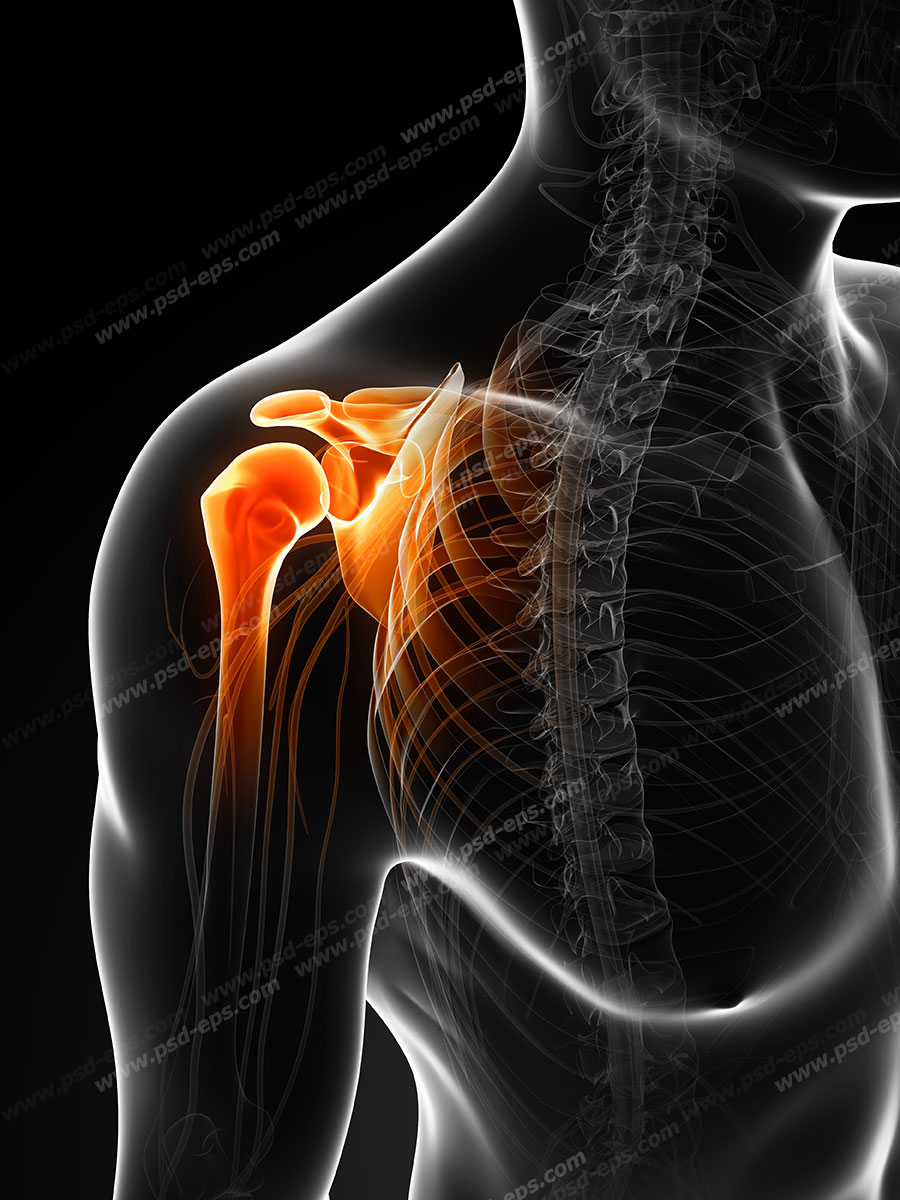

اسکلت داربست بدن است تمام قسمت های بدن روی اسکلت قرارگرفته اند بدن انسان از ۲۰۶ قطعه استخوان تشکیل شده است این استخوان ها طوری با نظم کنار هم قرار گرفته اند که انسان را قادر می سازد حرکات دقیقی داشته باشد. استخوان یک نسج بسیار محکم است زیرا در ترکیب آن منرالها مانند کلسیم و دیگر وجود. اسکلت داربست بدن است تمام قسمت های بدن روی اسکلت قرارگرفته اند بدن انسان از ۲۰۶ قطعه استخوان تشکیل شده است این استخوان ها طوری با نظم کنار هم قرار گرفته اند که انسان را قادر می سازد حرکات دقیقی داشته باشد. آناتومی سه بعدی بدن انسان عکس گرافی بدن امعاء و احشاء بدن آناتومی سه بعدی بدن انسان عکس گرافی بدن امعاء و احشاء بدن قلب کبد روده.